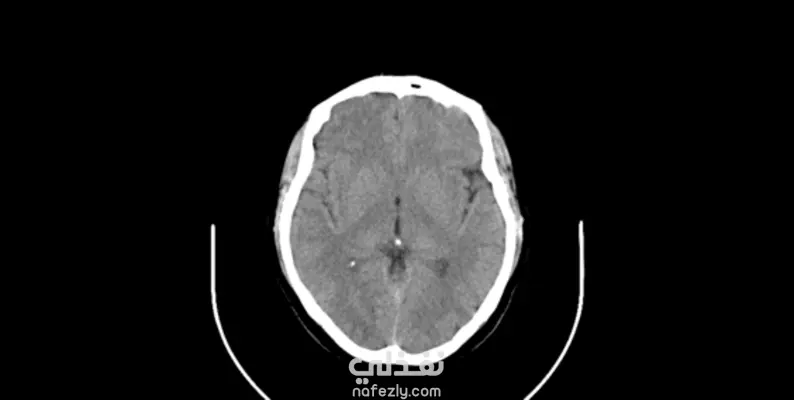

قمت بتطوير نموذج Semantic Segmentation مخصص لاكتشاف وتحديد مناطق أورام المخ في الصور الطبية باستخدام معمارية U-Net، وهي من أكثر النماذج استخدامًا في مجال Medical Image Analysis. المشكلة هي : تجزئة أورام المخ بدقة عالية من صور طبية رمادية (Grayscale MRI/CT) بهدف دعم التشخيص المبكر وتقليل الاعتماد الكامل على الفحص اليدوي.